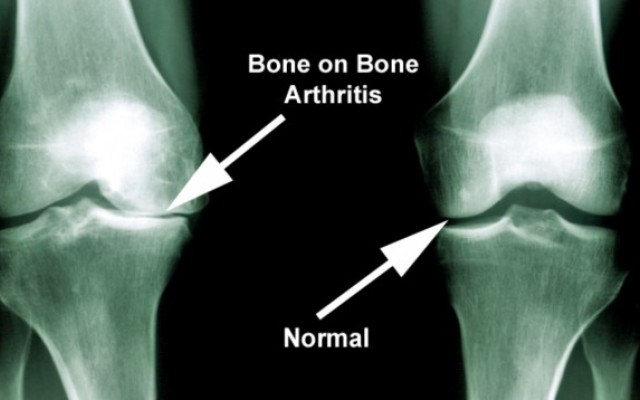

Attached video explains simply what osteoarthritis is and how it manifests as a painful condition.

Many people have knee replacements (also called knee arthroplasty) because they have osteoarthritis. This condition occurs when the cartilage (tissue) that cushions the knee joint wears away. As a result, bone...